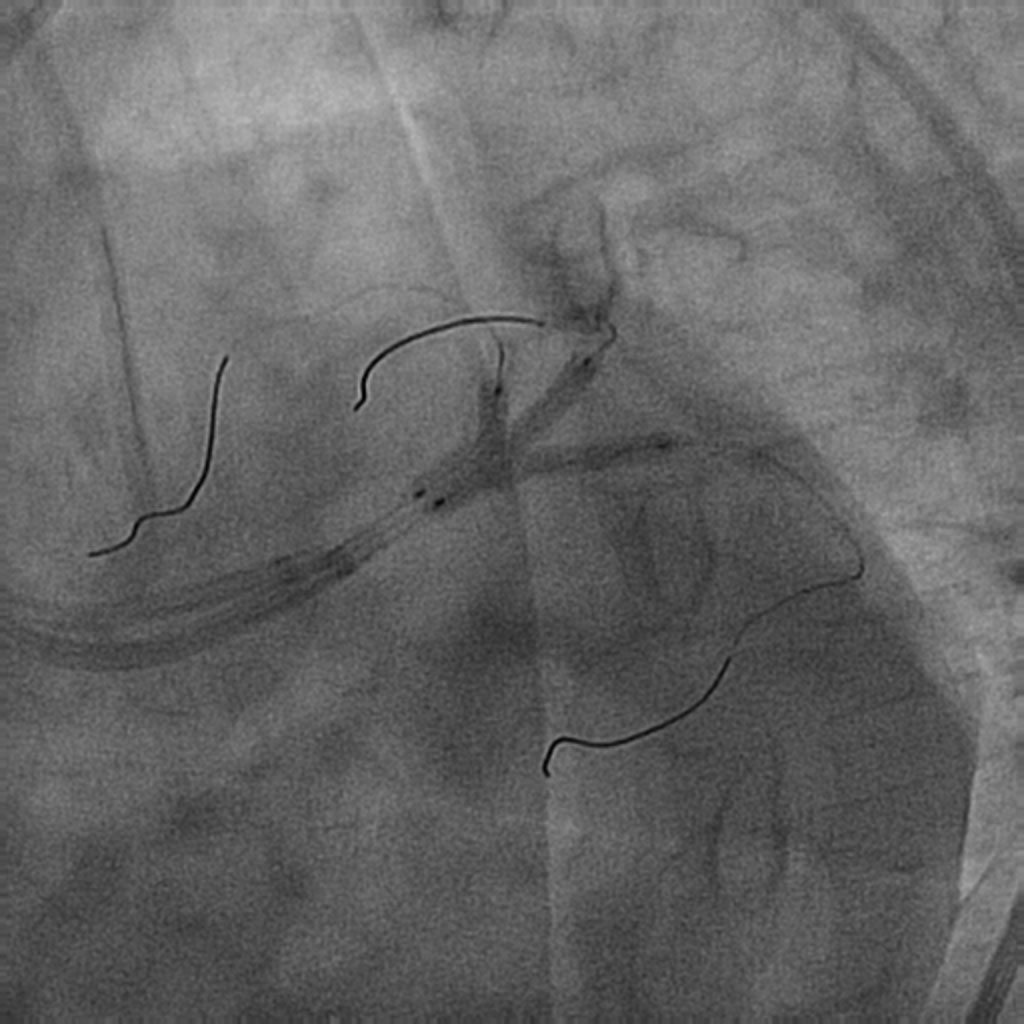

El procedimiento se efectuó bajo anestesia general, mediante abordaje femoral bilateral. Se colocaron 2 catéteres guía Extra Back Up (EBU) de 3,5 mm, de 6 y 7 Fr, en el tronco común izquierdo (técnica ping-pong). Se realizó predilatación secuencial de los ostia coronarios de la descendente anterior y las ramas intermedias mediante un balón de corte de 2,0 mm (vídeo 1 del material adicional) y se implantaron simultáneamente 3 stents farmacoactivos en la descendente anterior (stent liberador de sirolimus, de 2,25 × 15 mm), la primera rama intermedia (stent liberador de zotarolimus, de 2,25 × 18 mm) y la segunda rama intermedia (stent liberador de sirolimus, de 2,25 × 18 mm), por este orden; posteriormente se realizó un inflado simultáneo (figura 2). Por disección retrógrada se implantó un cuarto stent farmacoactivo (stent liberador de zotarolimus, de 4 × 8 mm) en el tronco común izquierdo (figura 3 y vídeo 2 del material adicional), con buen resultado por tomografía de coherencia óptica (figura 4A, B). Inmediatamente después de la intervención coronaria percutánea (ICP) se implantó una válvula aórtica expandible con balón de 23 mm (figura 5 y vídeo 3 del material adicional), también con buen resultado (figura 6 y vídeo 4 del material adicional).

Figura 2. Implante simultáneo de 3 stents farmacoactivos en la descendente anterior y las ramas intermedias.